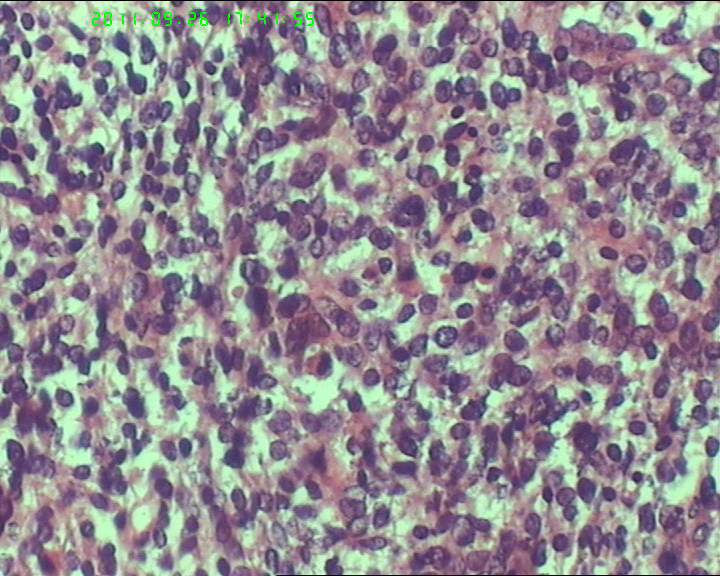

灰白不整形肿物一个,大小18*15*9cm,表面结节状,包膜完整,切面灰白,中央可见坏死区,质软,范围5*4cm。其余切面多彩 部分半透明状 质中。

鉴别诊断排排队:1、GIST,2、MPNST,3、去分化脂肪肉瘤,4、恶性间皮瘤,5、恶性SFT,6、平肉

主要考虑前二者。CD34,CD117,S-100,BCL-2,SMA, D2-40,CR, VIM. 结果如何?请楼主揭谜底吧。